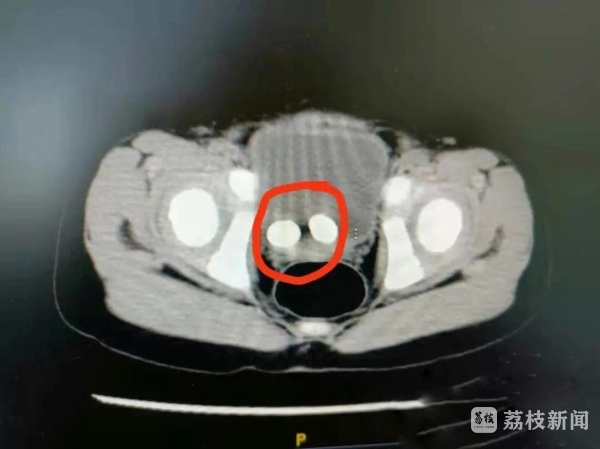

该院小儿泌尿外科顾绍栋主任接诊后,经仔细查体和CT诊断发现,小捷的膀胱里面竟然长了2个大结石。经询问,小捷妈妈告诉医生,小捷从来不喝水,天天疯跑玩得满头大汗也说自己不渴,大人虽然很着急,但孩子坚持说不渴,也就没太在意。

术中,顾绍栋通过2个小孔,将膀胱镜伸入后发现,小捷膀胱内的一枚结石直径约1.4厘米。顾绍栋熟练地将结石摘除后,再使用钬激光治疗仪将结石击碎成粉末排出体外,过程十分顺利。

但另一个结石却难住了他。术前的CT检查中,两个结石的位置似乎都是在膀胱中,但手术中发现其中一个1.4厘米的结石竟然隐藏在小捷左侧只有3-5毫米宽输尿管中。